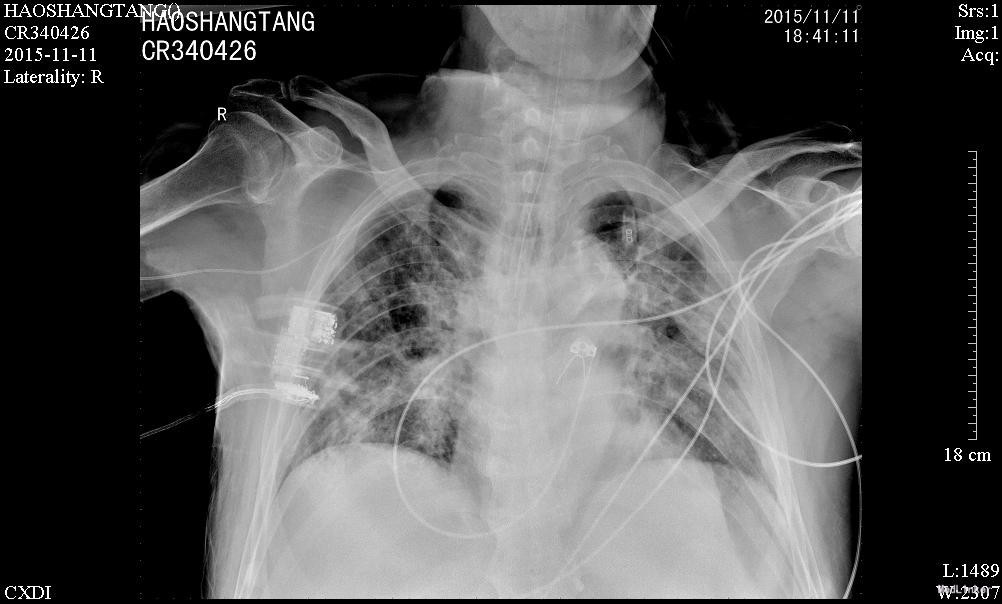

入神经内科经舒普深抗感染及抗癫痫等治疗,无明显癫痫,但肺部感染加重,查见广泛耐药鲍曼不动杆菌及铜绿假单胞菌感染,转入呼吸科后给予美平联合舒普深治疗,1周后成功拔管脱机,2周后体温完全正常,转入康复科继续治疗

患者高龄,合并多种疾病,又合并如此严重的感染,能够在短短半个月时间内获得如此好的疗效却确实很不容易,学习了